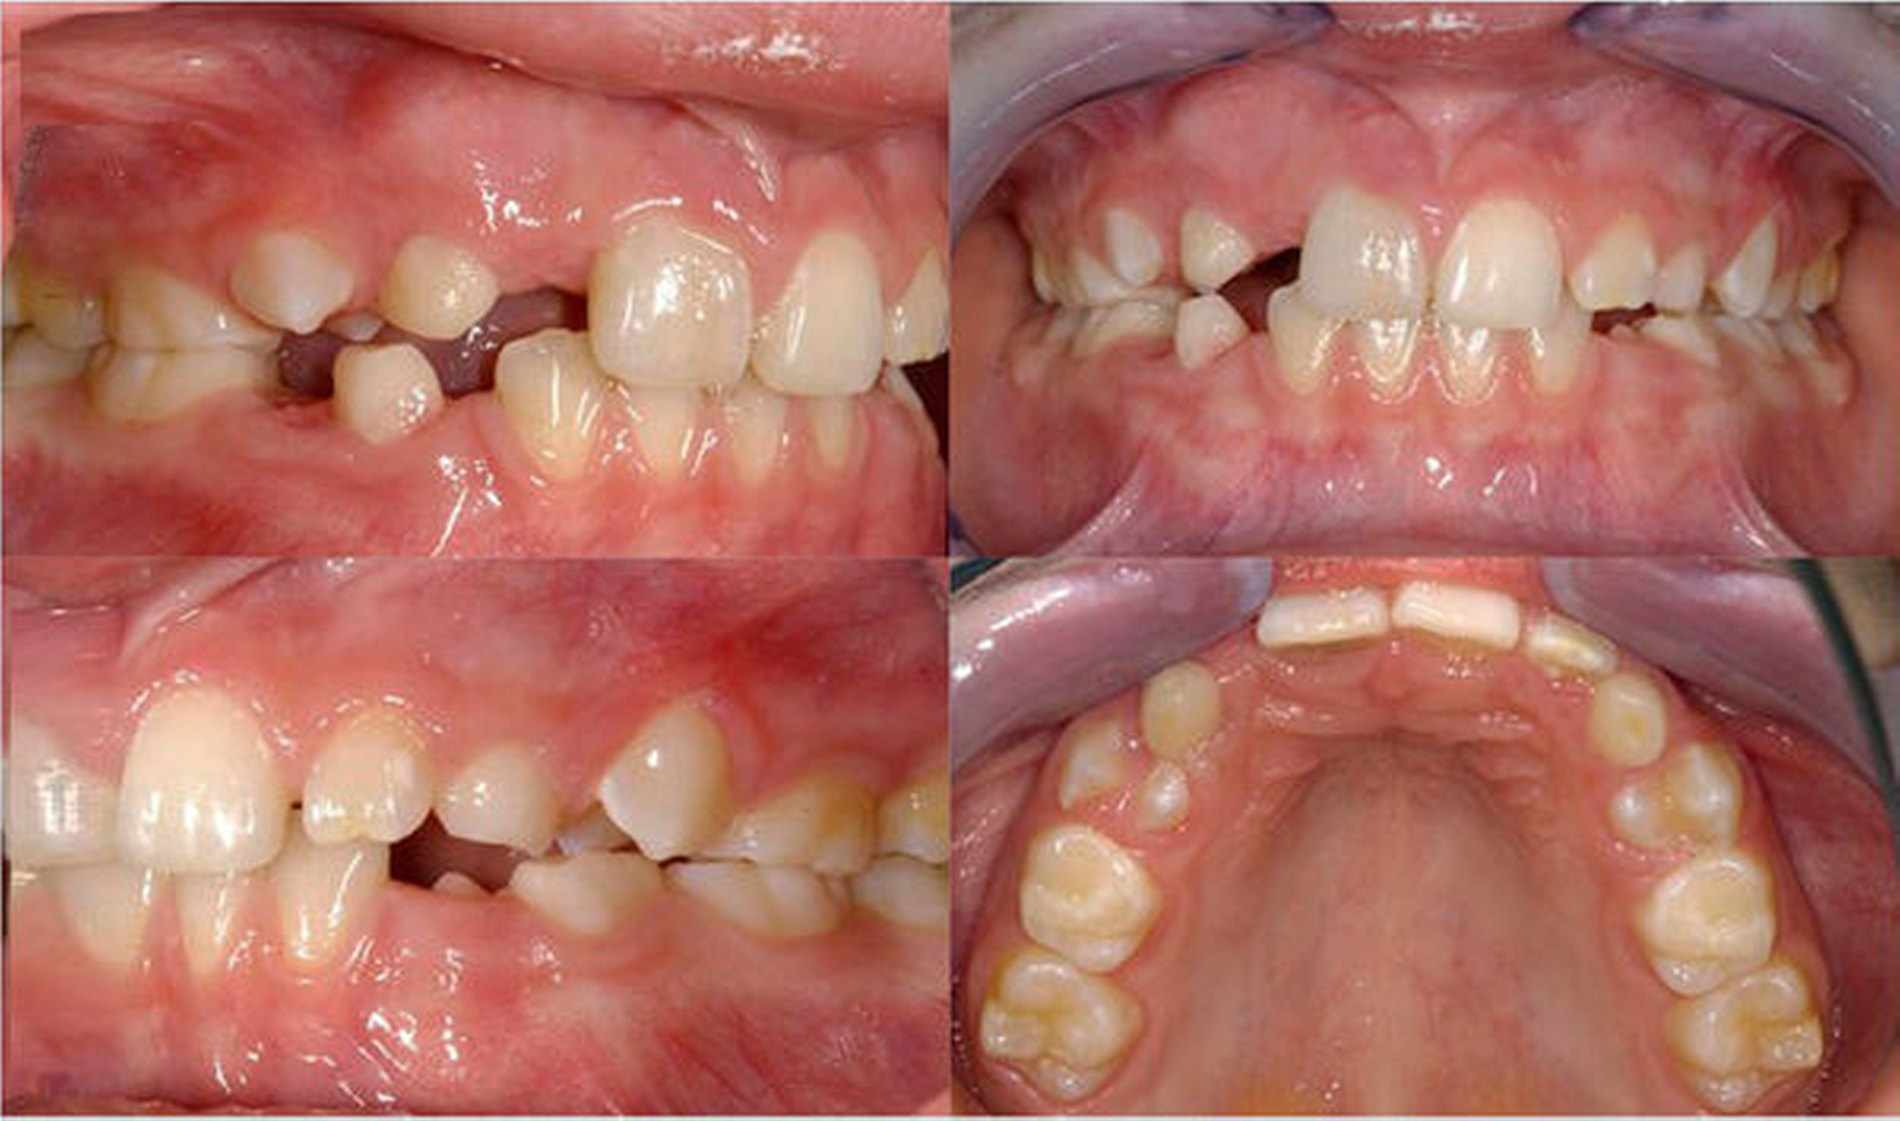

Die Häufigkeit für den Frontzahnverlust beträgt drei bis vier Prozent. Die Altersgipfel liegen zwischen dem achten und dem neunten sowie vom zwölften bis zum 14. Lebensjahr. Betroffene Zähne sind der mittlere und der seitliche Schneidezahn im Oberkiefer. Es besteht eine Korrelation der Häufigkeit zu den Zahnstellungsanomalien der vergrößerten sagittalen Schneidekantenstufe, dem schmalen Deckbiss mit protrudierten seitlichen Schneidezähnen und progen stehenden Einzelzähnen. Obwohl bei Avulsion die sofortige Reimplantation zum Erhalt des Zahnes führen kann, sind häufig Ankylosen des Parodonts und Wurzelresorptionen mit begrenzter Erhaltungswürdigkeit die Folgen. Eine fehlende Sensibilität, ein hoher Klopfschall und der röntgenologische Resorptionsnachweis sind diagnostische Anzeichen dafür.